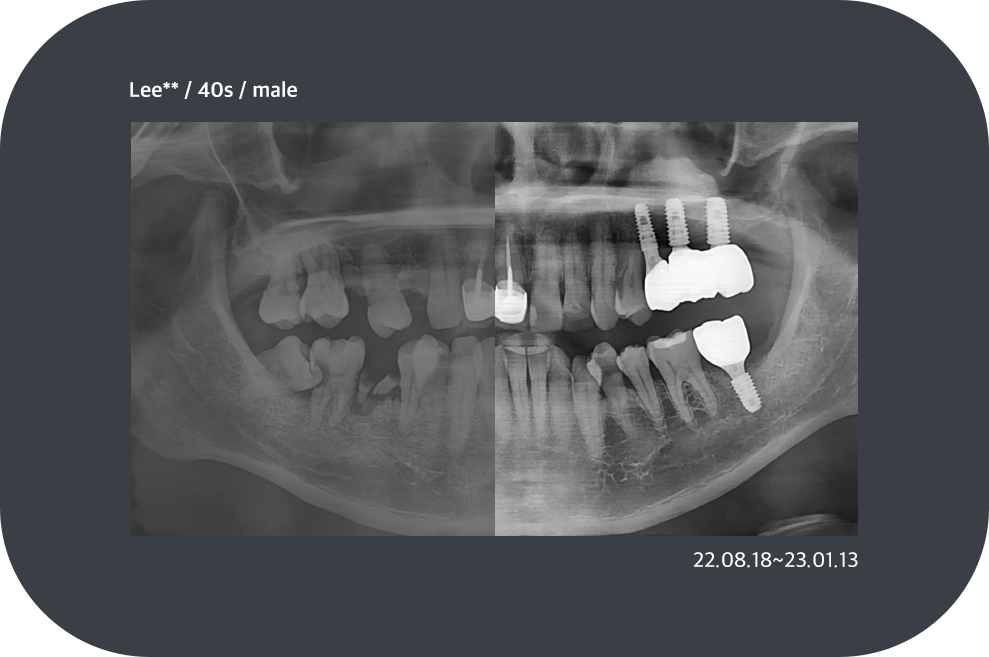

치료사례

임플란트 치료사례

*모든 증례 사진은 의료법 제23조, 제56조에 의거하여, 당사자의 동의하에 게시하였습니다.

*치료 사진은 모두 본원에서 치료한 환자분의 사진입니다.

*치료 사진은 모두 동일인의 사진이며, 동일조건에서 촬영하였습니다.

*개인의 차이에 따라 시술 및 수술 후 부작용이 발생할 수 있으며, 의료진과 충분한 상담을 받으시기 바랍니다.